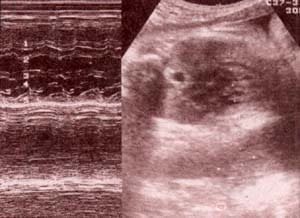

| fig 35. a nivel ventricular. 37 semanas. pared ventrículo derecho (1). válvula tricúspide (2). septum i-v (3). válvula mitral (4). pared ventrículo izquierdo (5). | fig 36. a nivel auricular. 32 semanas. pared aurícula derecha (1). válvula tricúspide (2). septum i-a (3). válvula mitral (4).pared aurícula izquierda (5). |

fig 37. a nivel del foramen oval. 36 semanas.

pared aurícula derecha (1). septum i-a (2).

válvula del foramen oval (3). pared aurícula izquierda (4).